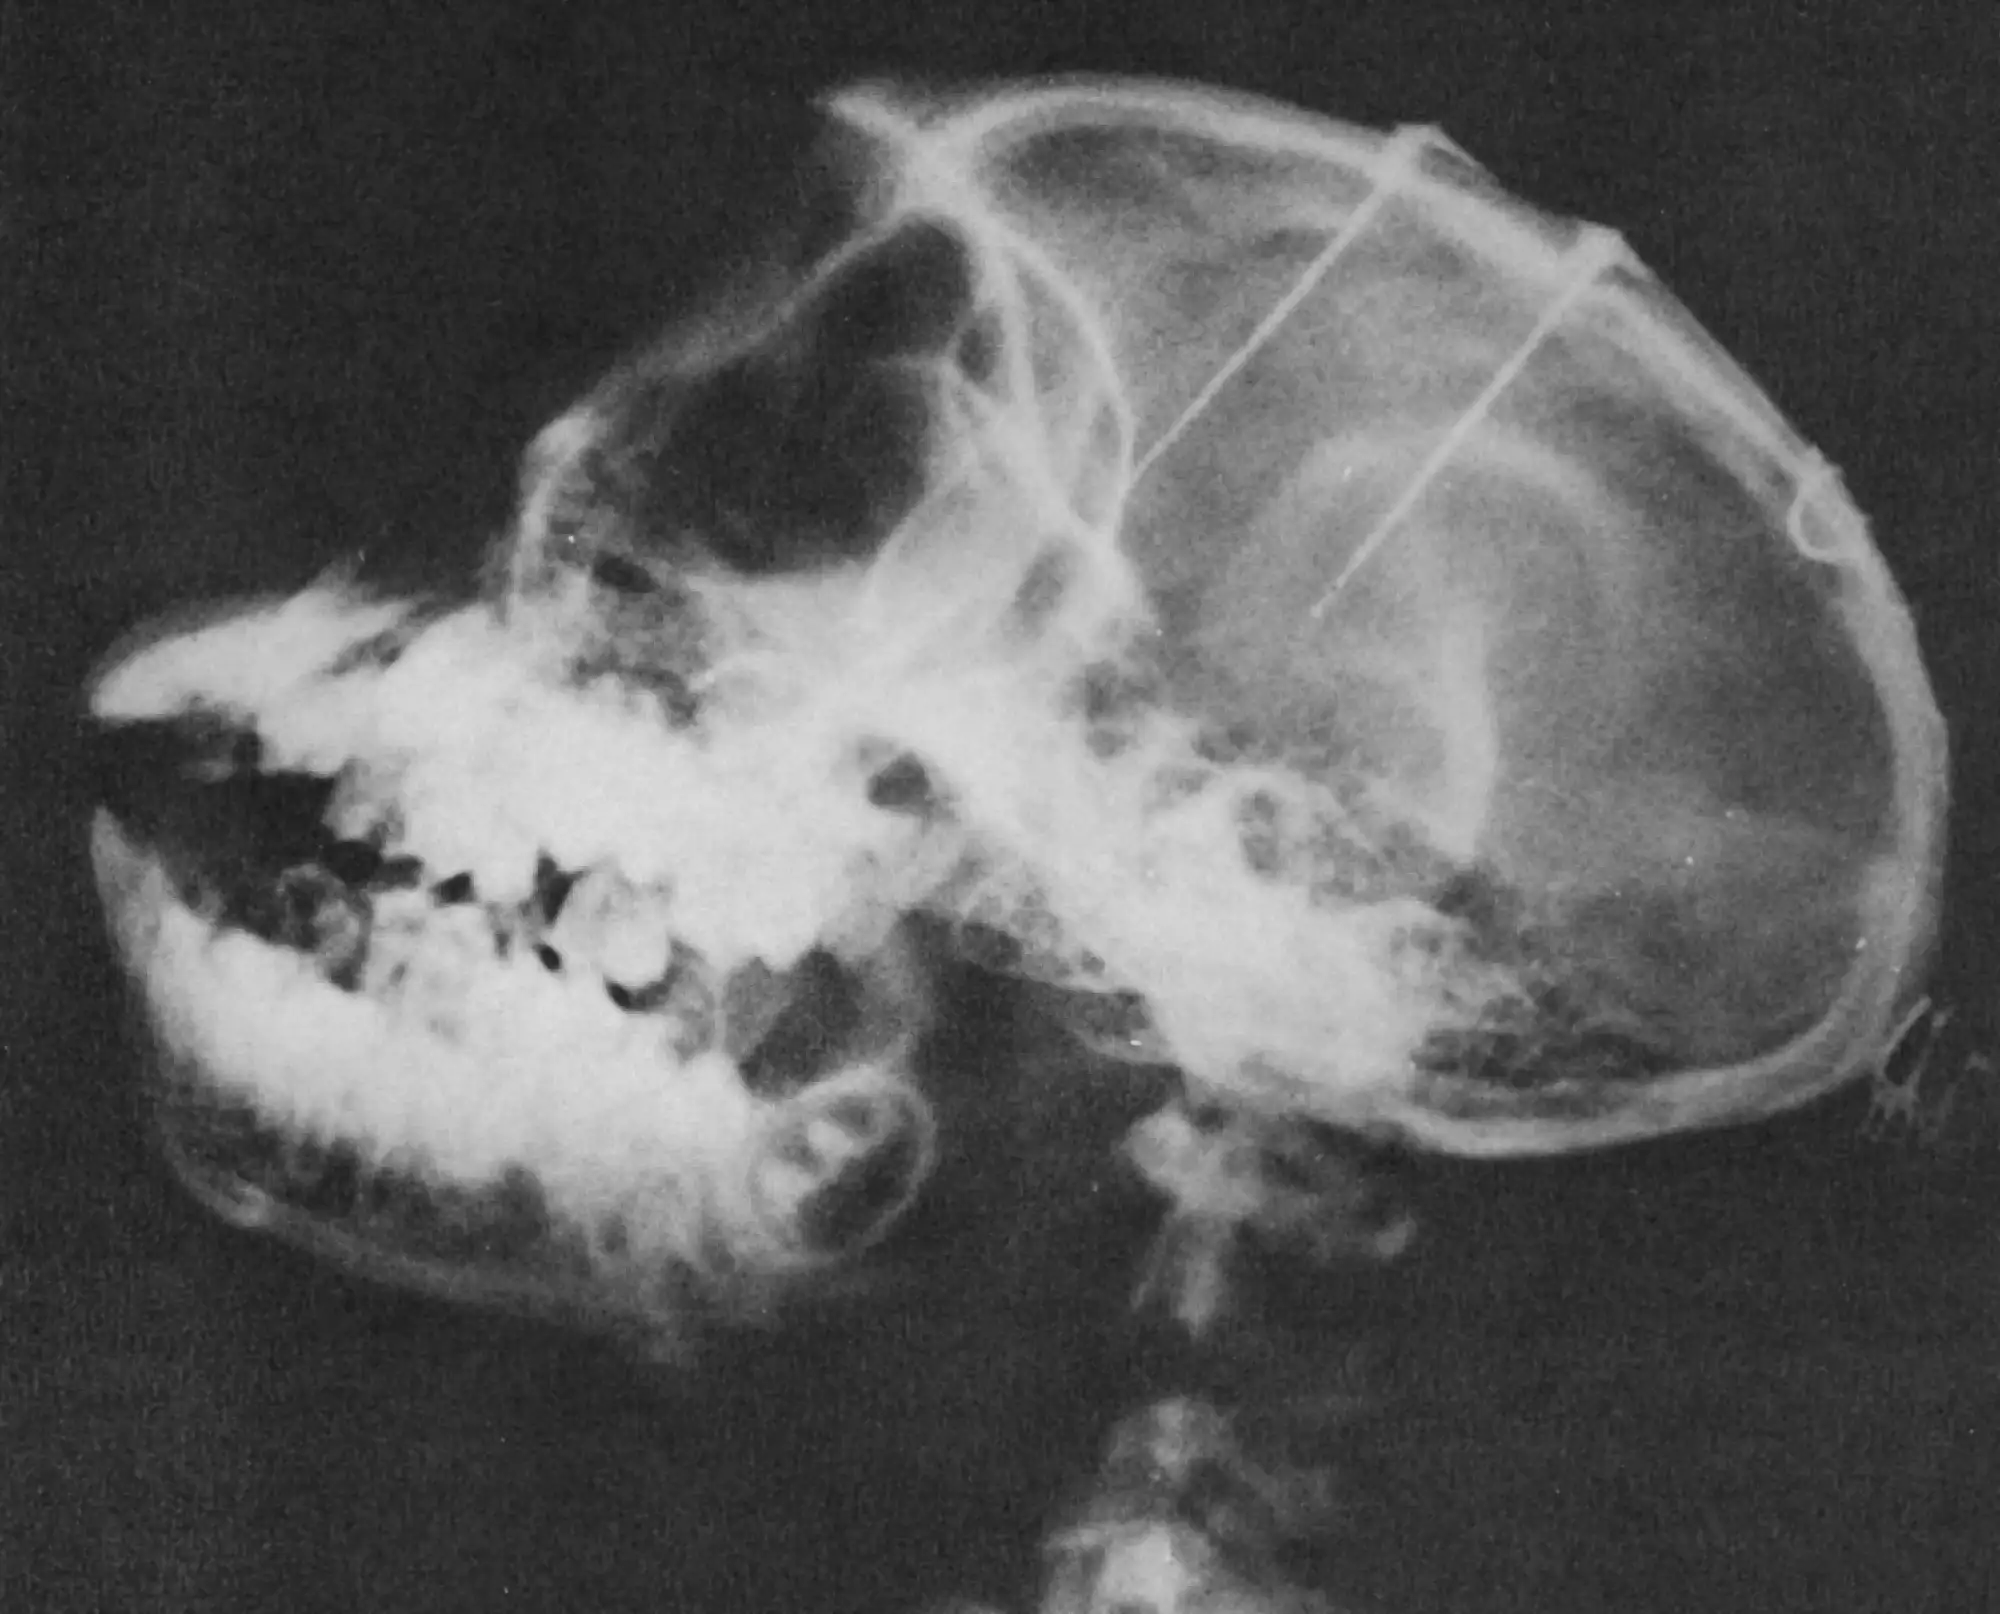

1964年,德尔加多在科尔多瓦省La Alamirilla牧场进行了他最著名的实验。牧场主人唐·拉蒙·桑切斯同意让德尔加多在几头公牛身上测试他的设备。

实验过程堪称"技术-田园-古典西班牙文化"的奇异混合。德尔加多用压缩空气枪将含有苯环己哌啶——一种NMDA受体拮抗剂,当时常用的动物手术麻醉剂——的注射器射入公牛体内。大约十五分钟后,公牛进入镇静状态。然后,德尔加多和牧场工人们暴露公牛的头骨,在每个大脑半球上方用手工钻头开一个直径两厘米的孔。

电极是直径0.1毫米的不锈钢丝,绝缘到尖端,以七根一束的形式集合在一起,每根电极在深度上相隔五毫米。因此,每个电极束可以覆盖七个位置,跨越三十毫米的范围,能够接触到初级运动皮层、基底神经节的尾状核和视丘。每头动物被植入十四到二十八个电极。

几天后,刺激试验开始。德尔加多使用他发明的手持无线电发射器,可以控制传输通道、电刺激脉冲频率(20-100赫兹)和刺激幅度(1-20伏特,相当于大脑中0.1-1毫安的电流)。